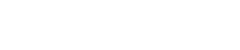

Implant Treatment: Your dentist prepares your implants within 3-7 days in line with radiographic measurements. The prepared implants are placed in your tooth in as little as 2 hours.

In order to apply fixed prosthesis in edentulous patients, 7-10 implants are needed in the upper jaw and 5-7 implants in the lower jaw. In general, 8 implants are applied to the upper jaw and 6 implants to the lower jaw.

Implant treatment is a long-term treatment type. Implant treatment for complete edentulism takes 2 hours, you will be checked after 1 week and stitches will be removed. After 3 to 6 months of waiting time for healing, your prostheses are made.